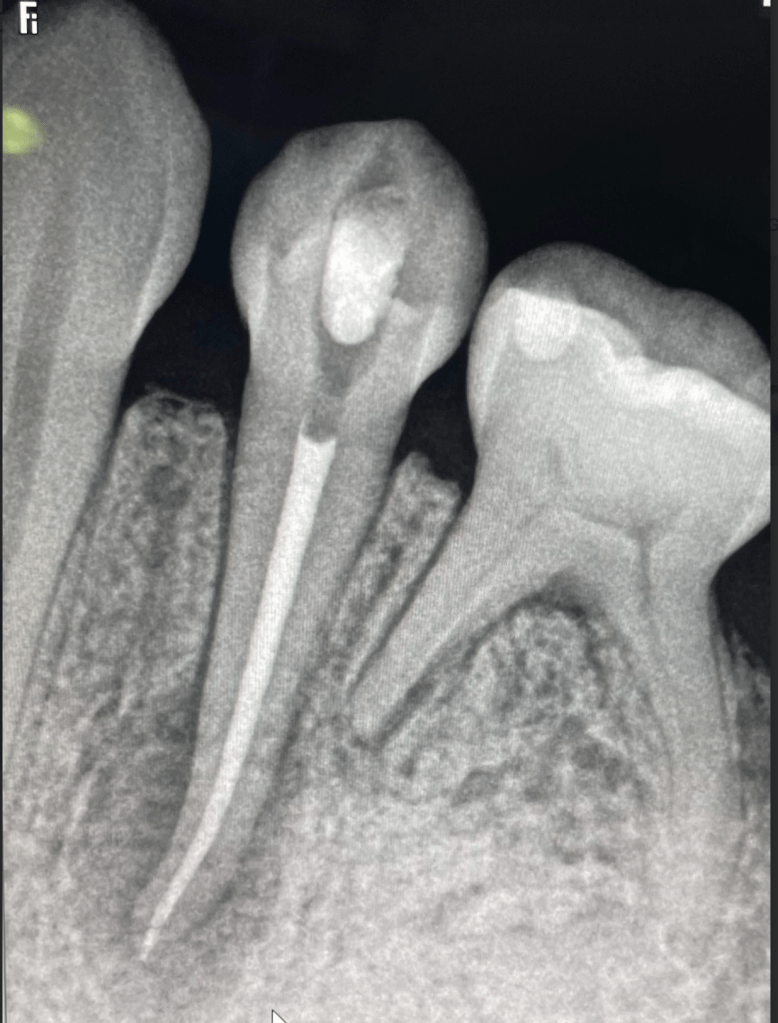

CALCIFICADOS

Premolar calcificado lesion